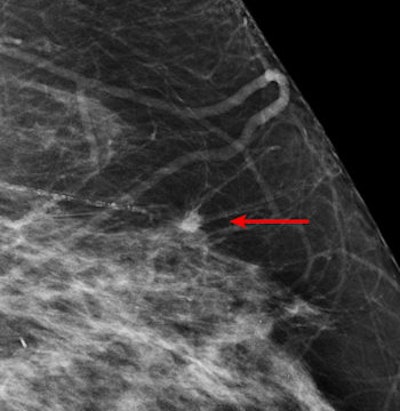

| An example of a study case with an invasive cancer not detected in the screening program. The cancer was detected by most radiologists in the study and by CAD. Image courtesy of Dr. Nico Karssemeijer. |

Many CAD systems also only target perceptual oversights, when misinterpreting suspicious regions may be a more common cause of missed malignant masses, according to the authors. As such, Hupse and colleagues looked at alternative ways to use CAD that help radiologists with interpretation of suspicious regions instead of exclusively focusing on avoiding oversight errors.